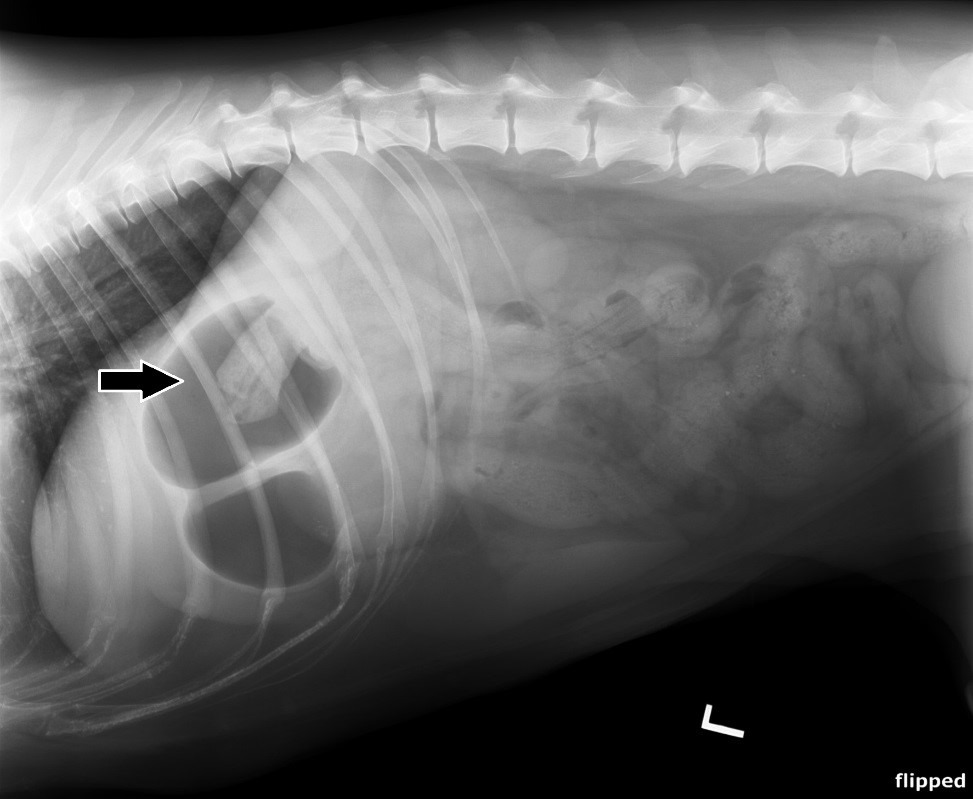

Veterinary Medical and Surgical Group San Juan. Young cats and young large-breed dogs are more likely to present with signs of foreign body obstruction than older animals. Often the foreign body cannot be seen on the x-ray but the consequences of the foreign body obstruction are visible. Clinical signs are variable depending on duration degree and location of the foreign body but often include vomiting and anorexia. Gastrointestinal foreign bodies are an important differential diagnosis for patients presented for vomiting and radiography remains the main initial imaging modality in these cases.

Young cats and young large-breed dogs are more likely to present with signs of foreign body obstruction than older animals. Several views or a series of specialized X-rays using contrast material barium or other radiographic dye will often be necessary. Black arrows define margins of suspected foreign material. They will pump air into his stomach or make use of Barium to locate any blockage. Often the foreign body cannot be seen on the x-ray but the consequences of the foreign body obstruction are visible.

The procedure used for foreign body removal in dogs will depend on the nature and location of the obstruction. These include fluid and gas building up behind or within the foreign body. Laguna Grove Veterinary Hospital Laguna Niguel Calif. When initial abdominal radiographs are equivocal for the presence or absence of gastrointestinal mechanical obstruction. Abdominal x-rays may be done to identify the foreign object and are useful for following the progression of the object through the GI tract.

Diarrhea weight loss lethargy and signs of septic. They will pump air into his stomach or make use of Barium to locate any blockage. In addition your veterinarian may recommend blood and urine tests to assess whether the patients health has been compromised by the obstruction or to rule-out other. Radiographs revealed a foreign body in a distended stomach. The procedure used for foreign body removal in dogs will depend on the nature and location of the obstruction.